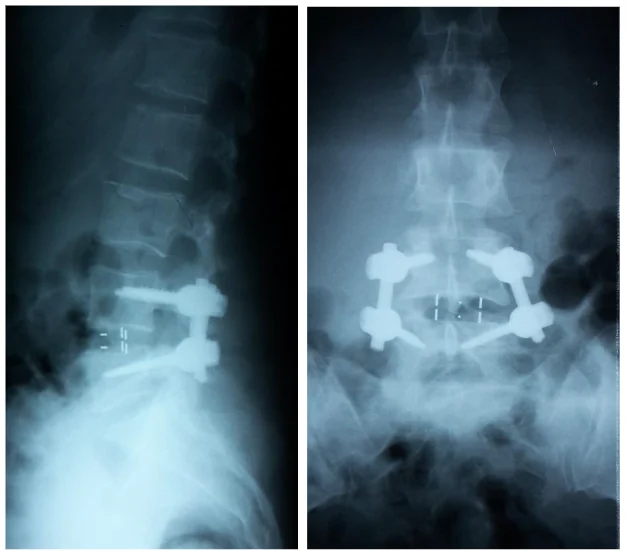

Radiografie din incidența laterală ce demonstrează spondilolisteza L4-L5 la o pacienta în vârstă de 54 ani.

Radiografii din incidența anteroposterioară şi laterală ale unui pacient cu spondilolistezis L4-L5 ce a suferit o intervenție chirurgicală de decompresie şi fuziune intercorporeala posterioară cu șuruburi pediculare și două cage-uri (TLIF)

Radiografii din incidența anteroposterioară și laterală ale unui pacient cu spondilolistezis L4-L5 ce a suferit o intervenție chirurgicală de decompresie și fuziune intercorporeala posterioară transforaminala cu șuruburi pediculare și cage PEEK (PLIF)